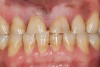

Figure 1   Classic presentation of the bruxism triad. Lateral wear pattern, generalized buccal tooth loss from erosion and abrasion, and history of sleep disruption.

Figure 1